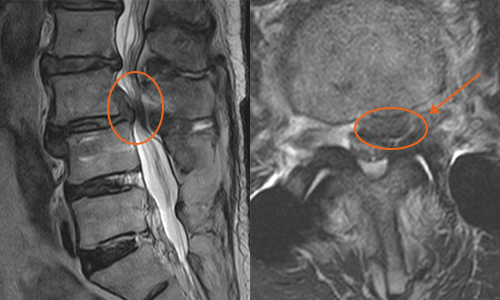

환자 : 65세 여성

증세 : 제 3,4번 요추간 돌출된 디스크와 비후된 황색 인대

경과 : 돌출된 디스크와 황색 인대가 제거된 결과, 비정상적인 신경의 신호가 하얗게 호전